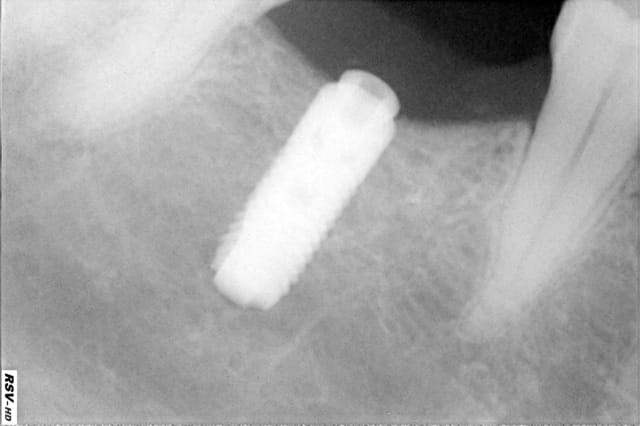

Voila j'ai revu mon patient ce soir. Plus de suppuration. Au niveau de l'oedème il a bien diminué, par contre il persiste un espèce de petit gonflement au fond du vestibule au niveau de 46 et 47, très légèrement sensible à la palpation. Aucune douleur et l'aspect de la gencive est satisfaisant. Reste plus que ce petit gonflement...

Si je pouvais me permettre une ou deux petites remarques ce serait : pourquoi changer d’AB sinon pour se rassurer et je trouve l’image de l’os à l’apex de ton implant (auto taraudant ?) un peu sombre

Ensuite pour l'image sous mon implant, elle s'explique assez simplement par un surforage d'un mm (emporté dans mon élan de joie... et surtout par un os dur comme du beurre après 1 heure au soleil) ce qui m'a ammené à faire du 2 temps d'ailleurs...

Dorie, le surforage en longueur est conseillé par certains ténors de la profession, donc dis leur que tu l'a fait exprés!

c'est vrai bravo si c'est vraiment le 1° (un ankylos non ???)

Dépose des fils aujourd'hui et tout est rentré dans l'ordre!! Pour la marque c'est un Astra.